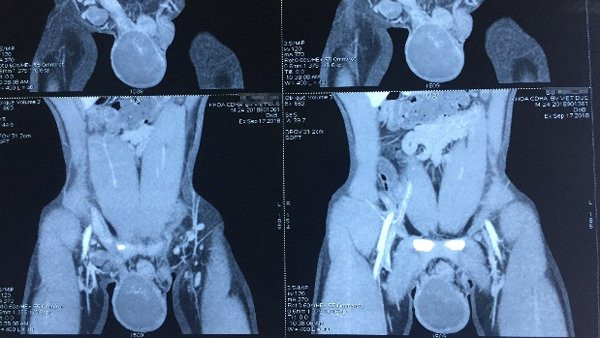

Kết quả kiểm tra cho thấy, bệnh nhân có tinh hoàn phải to chắc, ấn đau, biến đổi hình thái, tinh hoàn trái nhỏ. Hình ảnh chụp CT chỉ rõ hình ảnh u tinh hoàn phải chưa xâm lấn ra vỏ tinh hoàn và các tổ chức lân cận.

| Hình ảnh khối u trên tinh hoàn phải của bệnh nhân |